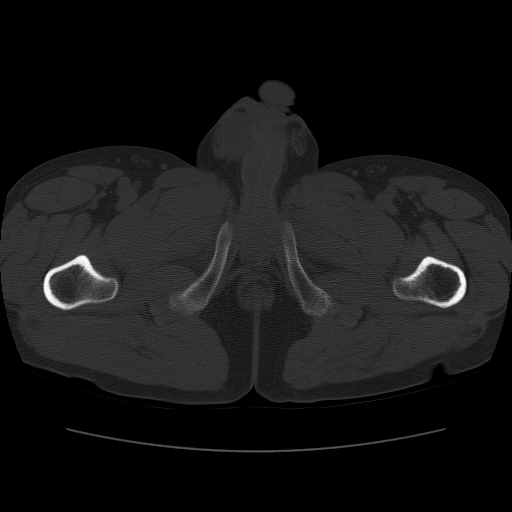

标题: CT11650:左髋病变,请会诊. [打印本页]

标题: CT11650:左髋病变,请会诊.

左髋疼痛不适近半年,局部无红肿热.无明确外伤病史.黄酒每天二餐.

考虑左侧股骨头缺血性坏死.(常期饮酒引起代谢障碍?)

左侧股骨头缺血性坏死;很典型。

“局部无红肿热.无明确外伤病史.黄酒每天二餐”。考虑左侧股骨头缺血性坏死。